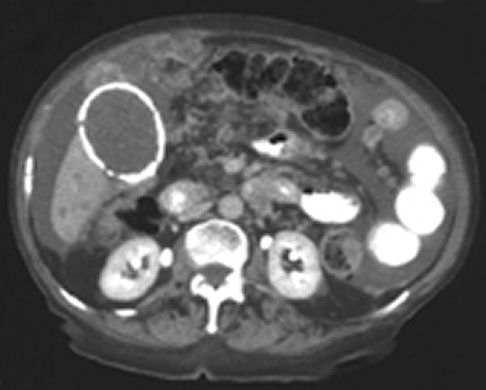

A computed tomographic scan showed that the calcification seen on the plain abdominal radiograph represented the wall of

the gallbladder (image below). The scan also showed ascites, multiple lesions in the liver, and nodularity of the

peritoneum and small bowel mesentery. These findings suggested metastatic carcinoma of the gallbladder, but the patient

refused further investigation.